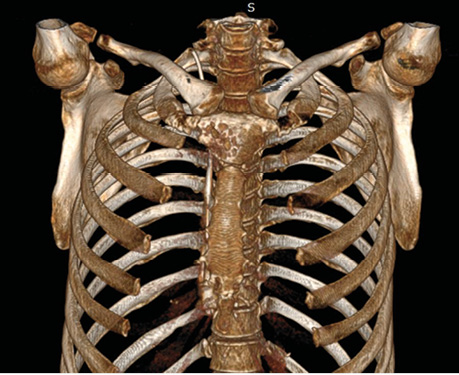

Післяопераційну 3D-реконструкцію КТ перед випискою пацієнтки наведено на рис. 6.

Рис. 6. Післяопераційна 3D-реконструкція КТ